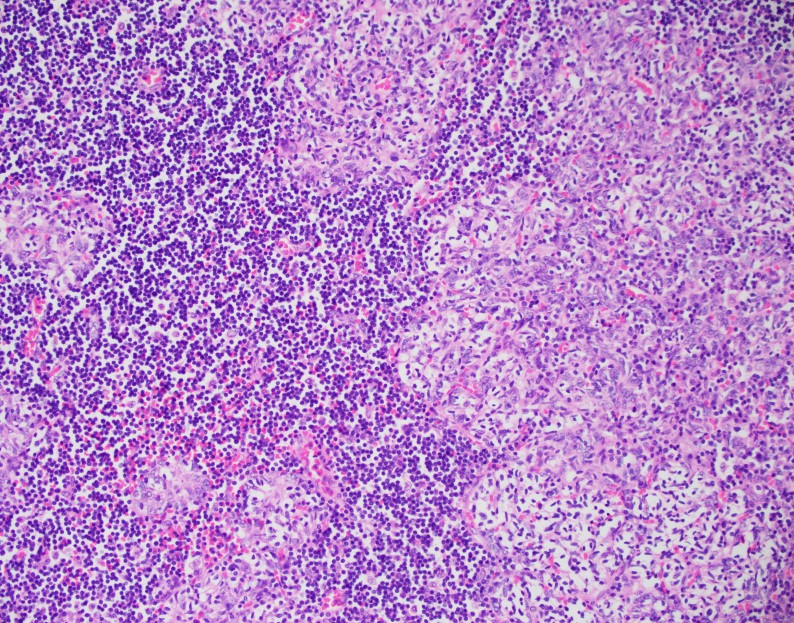

Tissue sections show a diffuse atypical lymphoid infiltrate that completely effaces the normal nodal architecture. The infiltrate is composed of numerous small lymphocytes with round to mildly irregular nuclei, clumped chromatin, inconspicuous nucleoli and scant cytoplasm. There are also expanded pale areas that contain intermediate sized cells with more open chromatin and distinct single to multiple nucleoli. These cells are most consistent with prolymphocytes/paraimmunoblasts and form the proliferation centers characteristic of CLL/SLL. Occasional centroblastic-type B-cells are noted within these proliferation centers. In addition, there are scattered single to multinucleated cells that have irregular nuclear membranes with pale, vesicular chromatin and prominent inclusion-like, eosinophilic nucleoli. These cells morphologically resemble Hodgkin cells, Reed-Sternberg cells, mummified forms and other variants. These large cells are more evident in areas with a histiocyte rich background and around foci of necrosis. Occasionally, apoptotic bodies and mitotic figures are seen.

Immunohistochemical studies show that the vast majority of the small-intermediate lymphocytes express B-cell markers CD20 (dim) and PAX5 and co-express CD5 and CD23 (subset). This is consistent with a background of CLL/SLL. The large atypical cells are positive for CD30, PAX5 and CD20 (variable). CD3 highlights numerous scattered background small T-cells, which are increased in the areas with the large cells. In situ hybridization for Epstein Barr viral RNA (EBER ISH) is mainly staining the large atypical cells. By Ki-67, the proliferation fraction is overall increased (40%) with increased uptake by the large atypical cells.

The morphologic and immunophenotypic findings are consistent with involvement by the patient’s known small lymphocytic lymphoma/chronic lymphocytic leukemia (SLL/CLL) with aggressive morphological features. The aggressive features include expanded proliferation centers and an elevated Ki-67 proliferative index (40%). Additionally there are histiocyte/T-cell rich areas composed of multiple EBV positive large atypical cells with morphologic and immunophenotypic features compatible with Hodgkin/ Reed-Sternberg cells. These areas are most in keeping with evolving classic Hodgkin lymphoma. Sheets of large cells indicative of large cell transformation are not seen, although increased scattered large centroblastic-type B cells are present.

Lymph node involvement by CLL/SLL will typically show a diffuse proliferation of small lymphocytes with effacement of the normal nodal architecture. The small lymphocytes have round nuclei, clumped chromatin and scant cytoplasm. Scattered paler areas known as proliferation centers are characteristic of this entity. The proliferation centers are composed of a mixture of cell types including small lymphocytes, prolymphocytes and paraimmunoblasts. Prolymphocytes are small to medium in size with relatively clumped chromatin, whereas paraimmunoblasts are larger cells with round to oval nuclei, dispersed chromatin, eosinophilic nucleoli and slightly basophilic cytoplasm. Some cases show increased and enlarged proliferation centers with a higher proliferation rate. This must be distinguished from large cell transformation.1